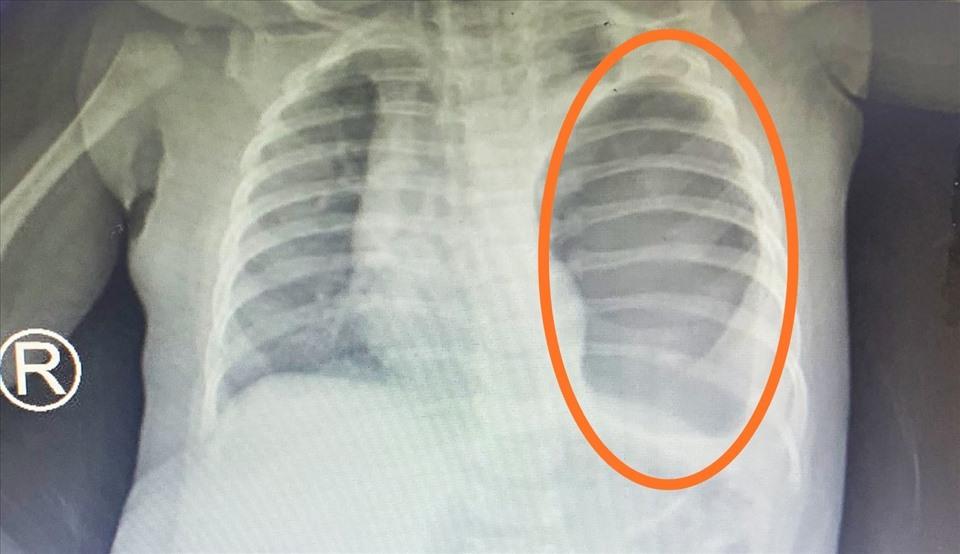

Tại bệnh viện địa phương, kết quả chụp chiếu ghi nhận bé chấn thương phần mềm phần đầu thái dương bên phải, nhưng nguy hiểm hơn là ghi nhận thoát vị hoành qua X-quang phổi. Bệnh nhi lập tức được chuyển lên Bệnh viện Nhi đồng Thành phố (TP.HCM).

Theo Thanh Niên cho biết, kết quả xét nghiệm, siêu âm ổ bụng và chụp X-Quang của bé cho thấy hình ảnh dạ dày, quai ruột chiếm toàn bộ phổi trái, chèn ép đẩy lệch tim sang bên phải. Chẩn đoán bị thoát vị hoành nếu không được mổ kịp thời để sắp xếp lại vị trí các tạng trong ổ bụng và lồng ngực, bé có thể tử vong bất kỳ lúc nào.